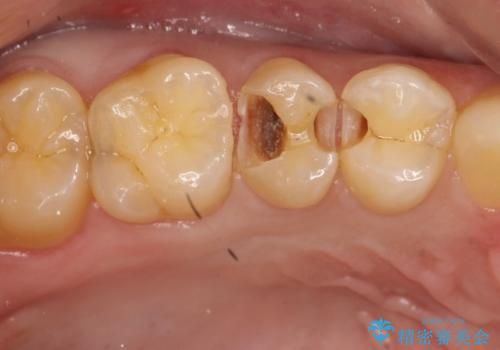

- 時々冷たいものがしみるといらした患者様です。

歯科医院に行くこと自体が久しぶりだったようで、口腔内にはたくさん虫歯がありました。

小さな虫歯に関しては保険内の白い詰め物にて、虫歯の大きい箇所はセラミックインレーにて修復しました。